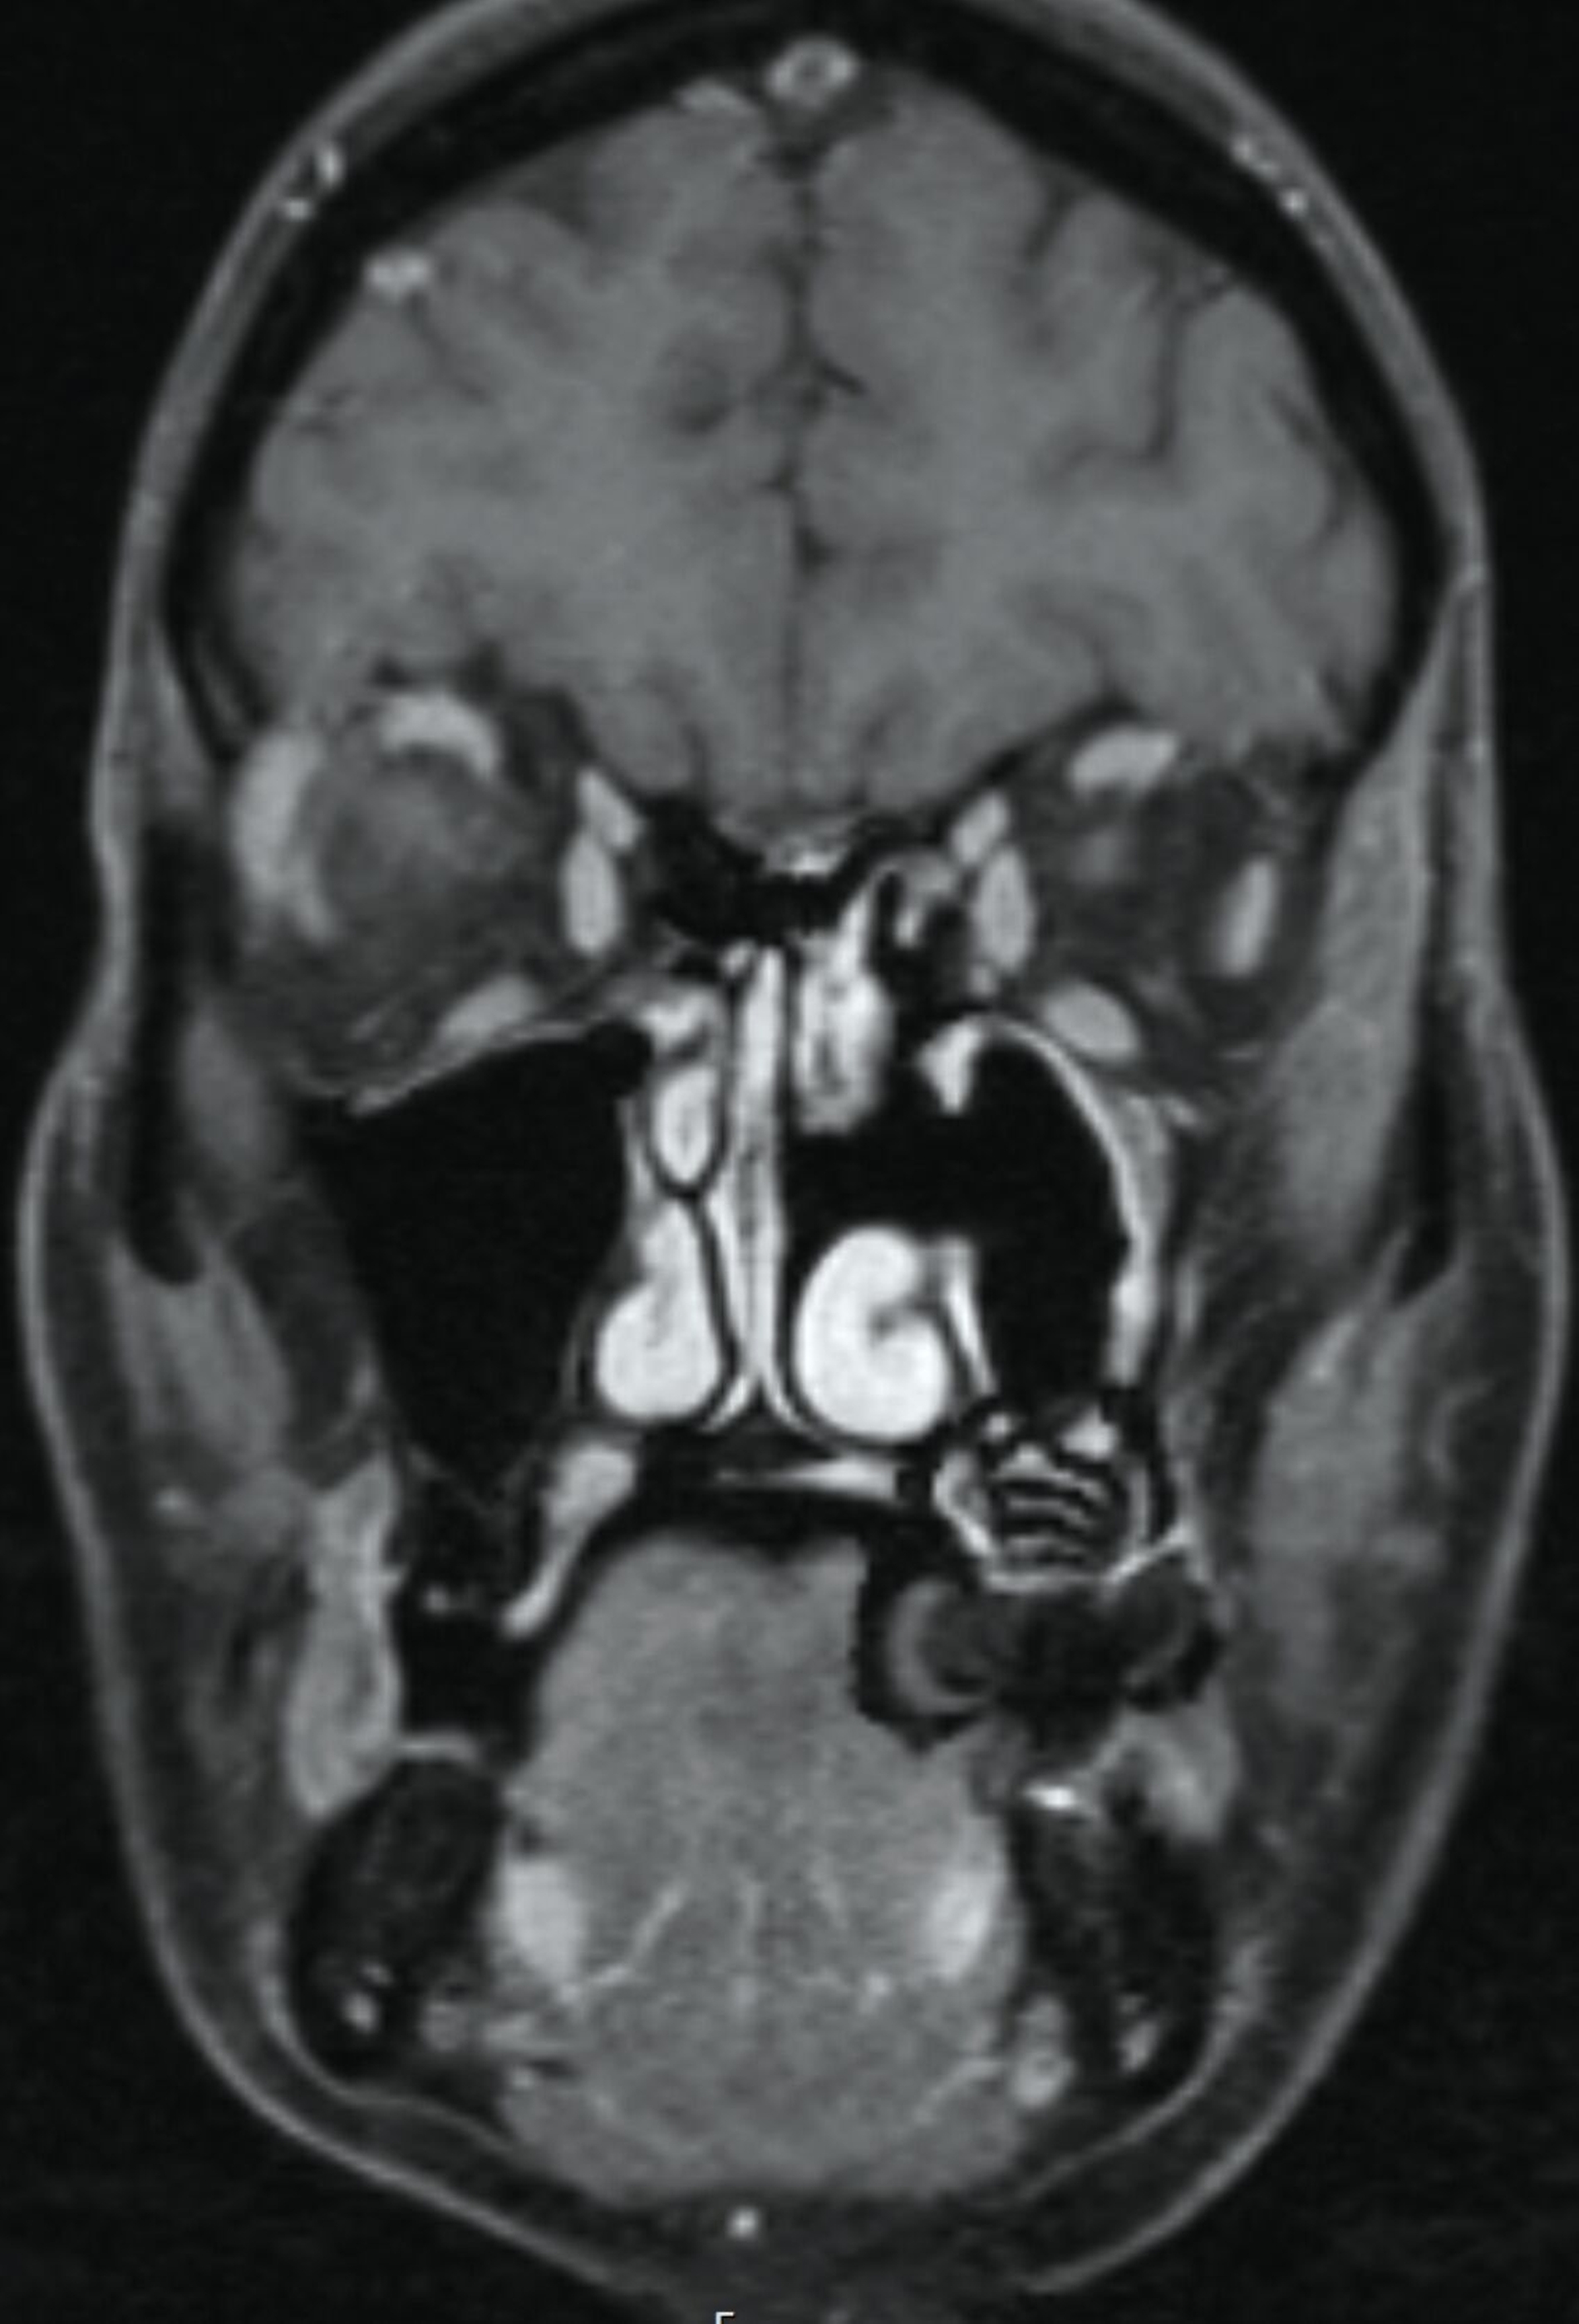

Im Verlauf stellte sich die Patientin trotz stringent eingehaltener Medikation mit erneut verstärkten Schmerzepisoden vor. Die Patientin assoziierte dies mit im Bereich der Kiefer – infolge einer im Vorfeld erfolgten Operation – vorhandenem Osteosynthesematerial zur Re-Fixierung des Kieferhöhlendeckels alio loco. Dies war von eitrigem Ausfluss aus der linken Nase begleitet. In der erweiterten Bildgebung mittels Magnetresonanztomografie zeigte die Patientin eine diffuse Kontrastmittelanhebung des Nervus infraorbitalis bildmorphologisch einer Neuritis entsprechend sowie eine diffuse Kontrastmittelanhebung des kranio-lateralen Kieferhöhlenknochens, teils mit Destruktion der kortikalen Strukturen, was den Verdacht einer Osteomyelitis nahelegte (Abbildung 4). Im zusätzlich angefertigten DVT konnte der Verdacht auf basale Aufhellung des linken Kieferhöhlenbodens bestätigt werden (Abbildung 5). Um eine definitive antimikrobielle Therapie und Diagnosesicherung zu ermöglichen, wurde die Entscheidung zur endoskopischen Probeentnahme gestellt.